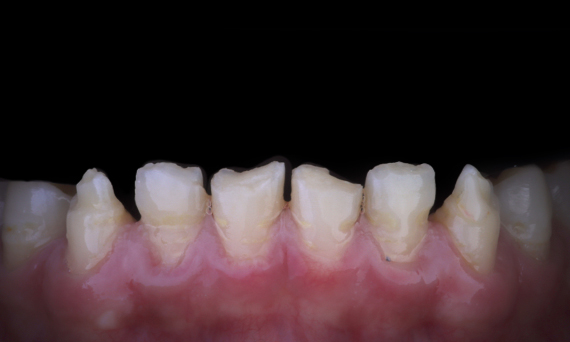

Amelogenezis İmperfekta Estetik Rehabilitasyon

CEREC Tessera

Celtra Ceram ile vener uygulanmış laboratuvarda CEREC Tessera restorasyonları ile anterior bölgede estetik rehabilitasyon gerçekleştirilebilir.

Önce: Tedavinin amacı, estetik iyileşme için anterior maksilla ve mandibulanın rehabilite edilmesiydi. Klinik tanıda amelogenezis imperfekta saptandı.

Sonrasında: İleri lityum-disilikat seramik CEREC Tessera’dan ve yüksek estetik sonuç için Celtra Ceram ile vener uygulaması ile yapılmış laboratuvar tarafından imal edilmiş restorasyon.

Sabine Mayer (CDT)

Koblenz, Almanya

Mario Pace (CDT)

Lahnstein, Almanya